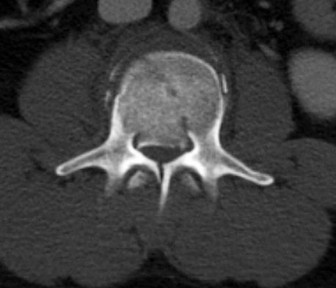

Question 4:

A 65-year-old man presents with progressive hand clumsiness and broad-based gait over 6 months. Physical exam reveals bilateral Hoffmann signs and 3+ patellar reflexes. An MRI of the cervical spine is obtained. Which of the following specific MRI findings is most strongly predictive of a poor postoperative neurologic prognosis following surgical decompression for cervical spondylotic myelopathy?

Correct Answer: Low signal intensity on T1-weighted images

Explanation:

In cervical spondylotic myelopathy, a high signal on T2-weighted images often represents edema or gliosis and has a mixed predictive value. However, the presence of a corresponding low signal intensity on T1-weighted imaging indicates permanent cystic necrosis of the spinal cord (myelomalacia) and strongly correlates with a poor prognosis for neurologic recovery after decompression.